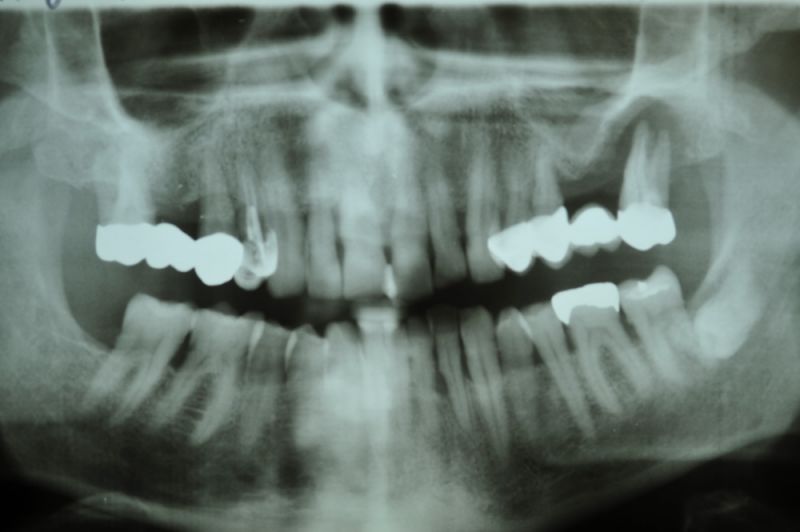

73 jähriger CMD-Patient im Recall

Der Patient hat vor 5 Jahren eine äußerst umfangreiche und komplexe CMD-Behandlung abgesclossen und befindet sich seitdem in einem engmaschigen vierteljährlichen Recall!

Seit 5 Jahren ist der Zustand des Patienten vollkommen unverändert!

Die aktuellen Taschentiefen liegen bei 2 Millimeter! Auch im Bereich der Implantate!

Das Allerwichtigste bleibt aber der engmaschige, vierteljähliche Recall, der aus mehr besteht, als nur einem Zahnsteinentfernen! Wichtig ist die fortlaufende Dokumentation der verschiedenen Parameter der parodontalen Gesundheit und genauso wichtig eine Röntgenkontrolle etwas alle ein bis eineinhalb Jahre.